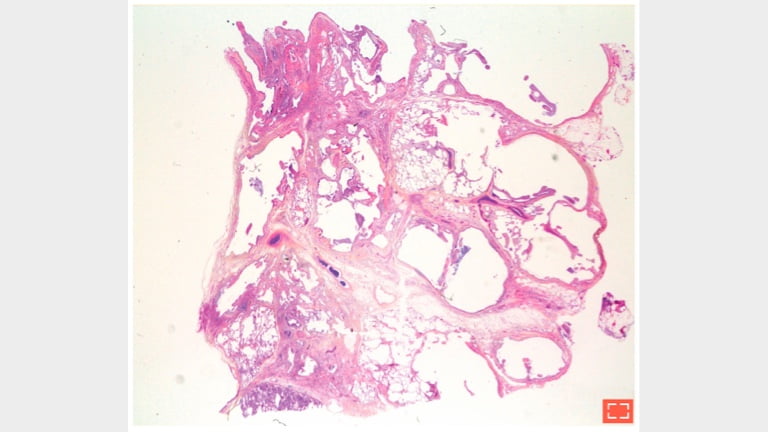

4. Less typical distribution of fibrosis: absence of normal nonfibrotic parenchyma

parenchyma@2x

5. Less typical distribution of fibrosis: absence of normal nonfibrotic parenchyma